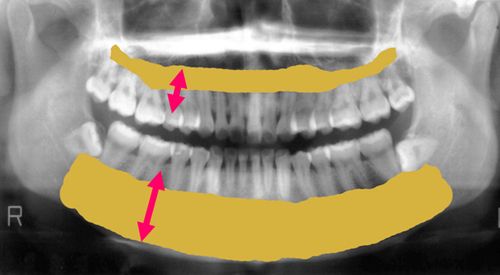

骨の病気ですので、診断にはまずはレントゲンの撮影が必要です。

もっと詳しく診断するにはCT装置による撮影を行い、

歯を支えている骨(歯槽骨)や顎の骨、

顎関節の状態まで確認することが必要になります。

骨が溶けるとはどういうことでしょうか。

よく分からないですよね。

歯の周りの骨が溶けるということです。

骨が溶けたら歯は支えられませんから歯が抜けます。

骨が溶けるということはその場のその歯の骨だけが溶けるということではないのです。

骨は繋がっています。

隣の歯の骨まで溶かせます。